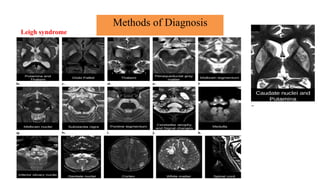

Brain magnetic resonance imaging

• Magnetic resonance imaging and spectroscopy are important tools in the diagnosis of

mitochondrial disorder.

• Brain atrophy is common in children with mitochondrial disease.

• Basal ganglia calcification are common in KSS and MELAS.

• Diffuse signal abnormalities of the white matter are characteristic of

KSS and myoneurogastrointestinal encephalopathy (MNGIE).

Methods of Diagnosis

Brain magnetic resonance imaging and spectroscopy

• The diagnosis of MELAS can be aided by the clinical association of stroke-like episodes with

radiological lesions that do not conform to the anatomical territories of blood vessels and

predominantly involve cortical gray matter.

• The initial or predominant lesions in MELAS are characteristically in the parietal- occipital

region.

• Leigh syndrome characteristically shows bilateral hyperintense signals on T2- weighted and

fluid-attenuated inversion recovery (FLAIR) MRIs in the putamen, globus pallidus and thalamus.

• MRS often detects lactate accumulation in the CSF and in specific areas of the

brain.

Leigh syndrome